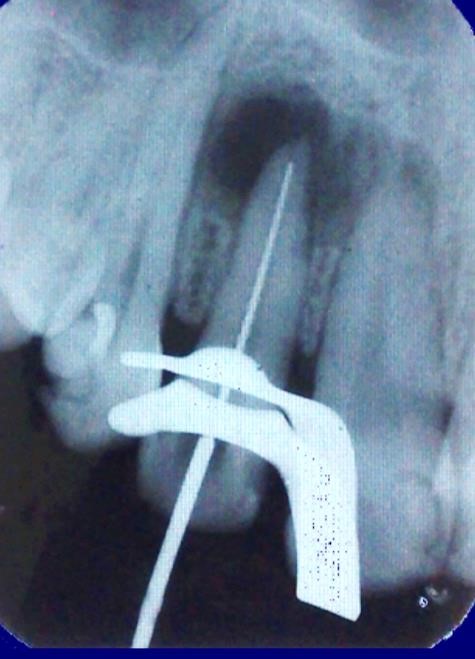

Após os procedimentos de antissepsia foi realizada anestesia do nervo alveolar superior, seguido de isolamento absoluto e remoção do tecido cariado com broca esférica nº 2 (KGSorensen, Cotia-SP, Brasil) em alta-rotação, posteriormente foi realizada a abertura coronária seguida de irrigação com solução de NaOCL a 2,5% e a exploração do canal com instrumento tipo K # 15 (Dentsply-Meillefer). O preparo coroa-ápice sem pressão: preparo cervical com as brocas Gattes Glidden em ordem decrescente de números 5, 4 e 3 irrigando com solução de NaOCL a 2%. O preparo cervico-medial com instrumentos manuais tipo K-Files (Dentsply-Meillefer®), em ordem decrescente: 2ª Série, # 80/#70/#60/#55/#50, a cada troca de instrumento realizou-se irrigação abundante com solução de NaOCL a 2%. Ao atingir o comprimento de 2mm aquém do ápice radicular, realizou-se a odontometria para a determinação do Comprimento Real de Trabalho e Comprimento Real do Dente (Figura 2).

Figura 2. Odontometria para a determinação do Comprimento Real de Trabalho.